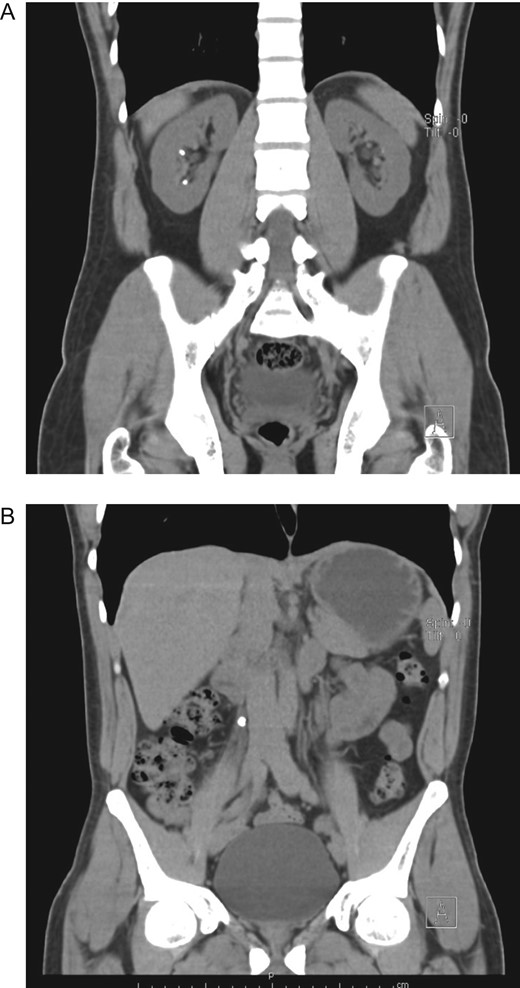

On clinical examination, a dehydrated and tachycardic patient was encountered. He had pain in his right flank that radiated to his lower abdomen and groin. Complete blood count (CBC) and urinalysis appeared normal, however, an abdominal computed tomography (CT) detected bilateral nephrolithiasis, multiple 5 mm, and 6 mm lesions were identified on both the right and left kidney. Also, a 7 mm hyperdense shadow in the middle of the right ureter that caused proximal hydronephrosis was detected as well (Fig. 1A and B).

(A) CT, revealing bilateral nephrolithiasis. (B) CT, with a 7 mm hyperdense shadow in the middle of the right ureter.